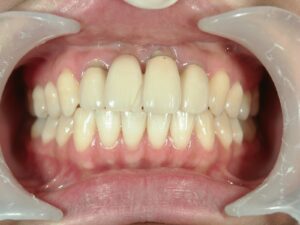

きれいな前歯が入りました。

患者さんは非常に満足されています。